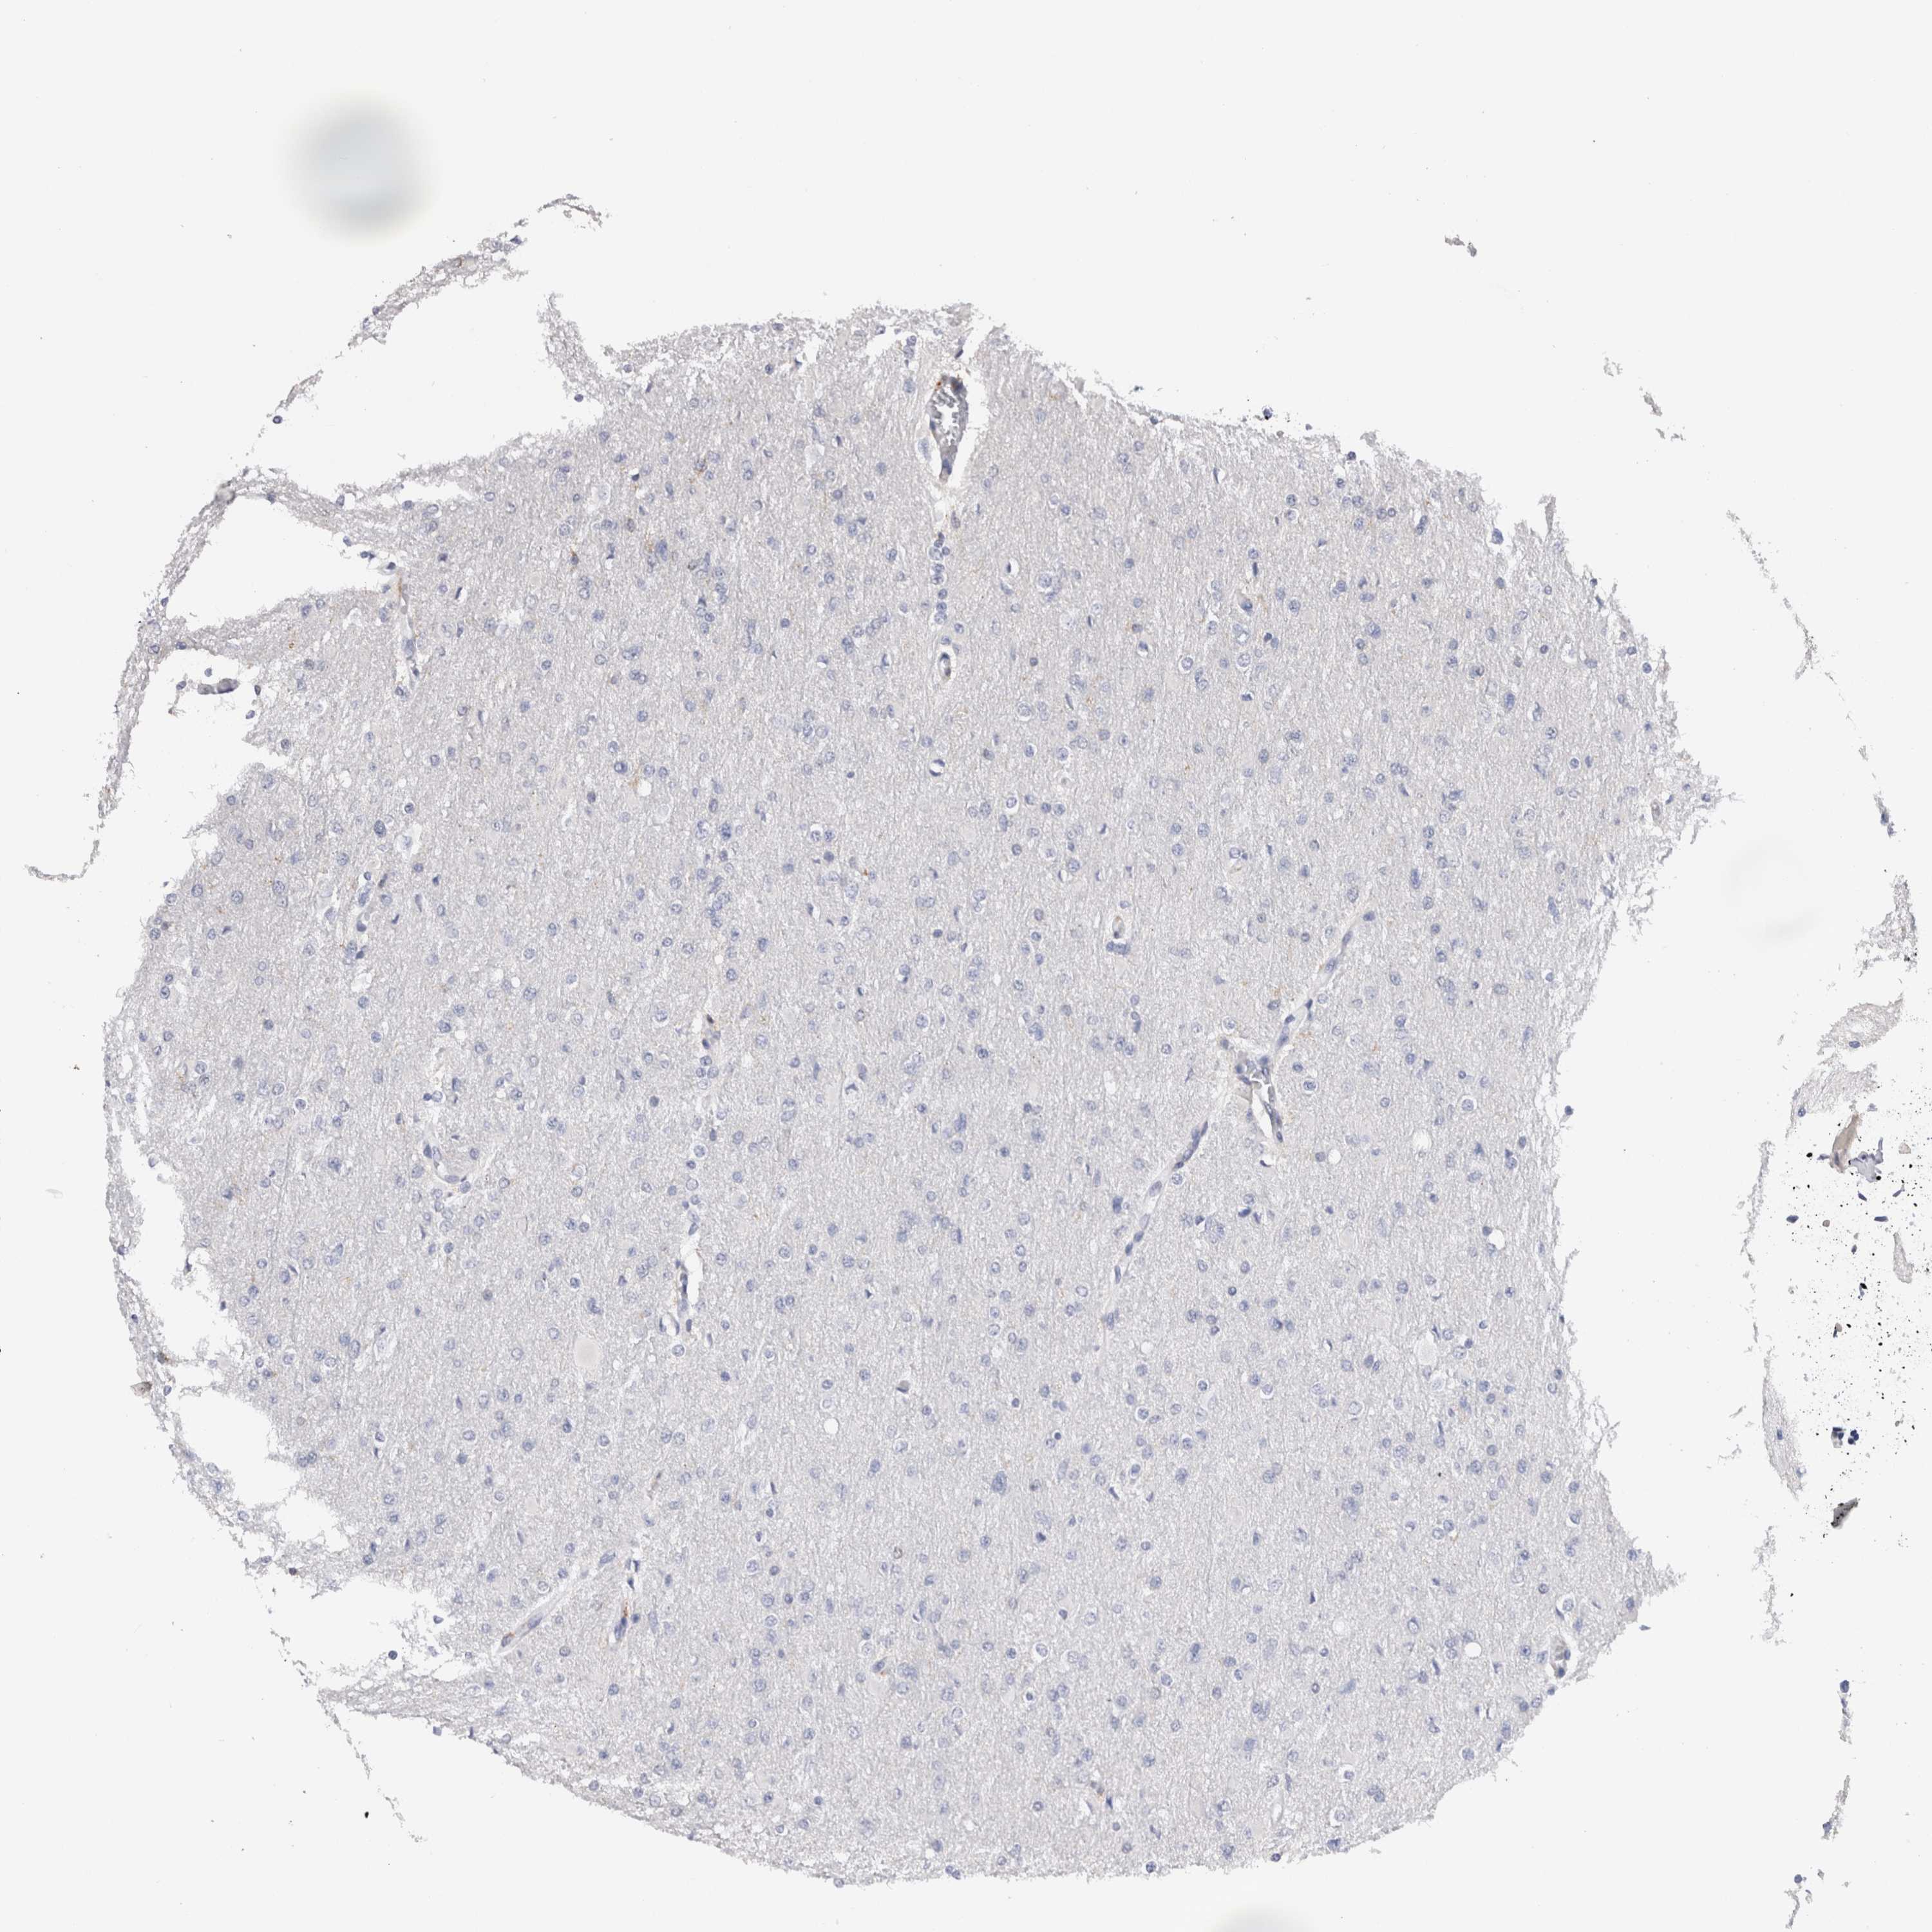

GLIOMA - Protein expressioni

A mouse-over function shows sample information and annotation data. Click on an image to view it in a full screen mode. Samples can be filtered based on level of antibody staining by selecting one or several of the following categories: high, medium, low and not detected. The assay and annotation is described here.

Note that samples used for immunohistochemistry by the Human Protein Atlas do not correspond to samples in the TCGA dataset.

Antibody stainingi

Antibody staining in the annotated cell types in the current human tissue is reported as not detected, low, medium, or high, based on conventional immunohistochemistry profiling in selected tissues. This score is based on the combination of the staining intensity and fraction of stained cells.

Each image is clickable and will lead to virtual microscopy that enables deeper exploration of all samples and also displays staining intensity scores, fraction scores and subcellular localization as well as patient and tissue information for each sample.

Antibody HPA003903

Antibody HPA072756

Antibody CAB026000

Staining

High

Medium

Low

Not detected

Intensity

Strong

Moderate

Weak

Negative

Quantity

>75%

75%-25%

<25%

None

Location

Nuclear

Cytoplasmic/membranous

Cytoplasmic/membranous,nuclear

Glioma, malignant, High grade

Glioma, malignant, NOS

Glioma, malignant, Low grade